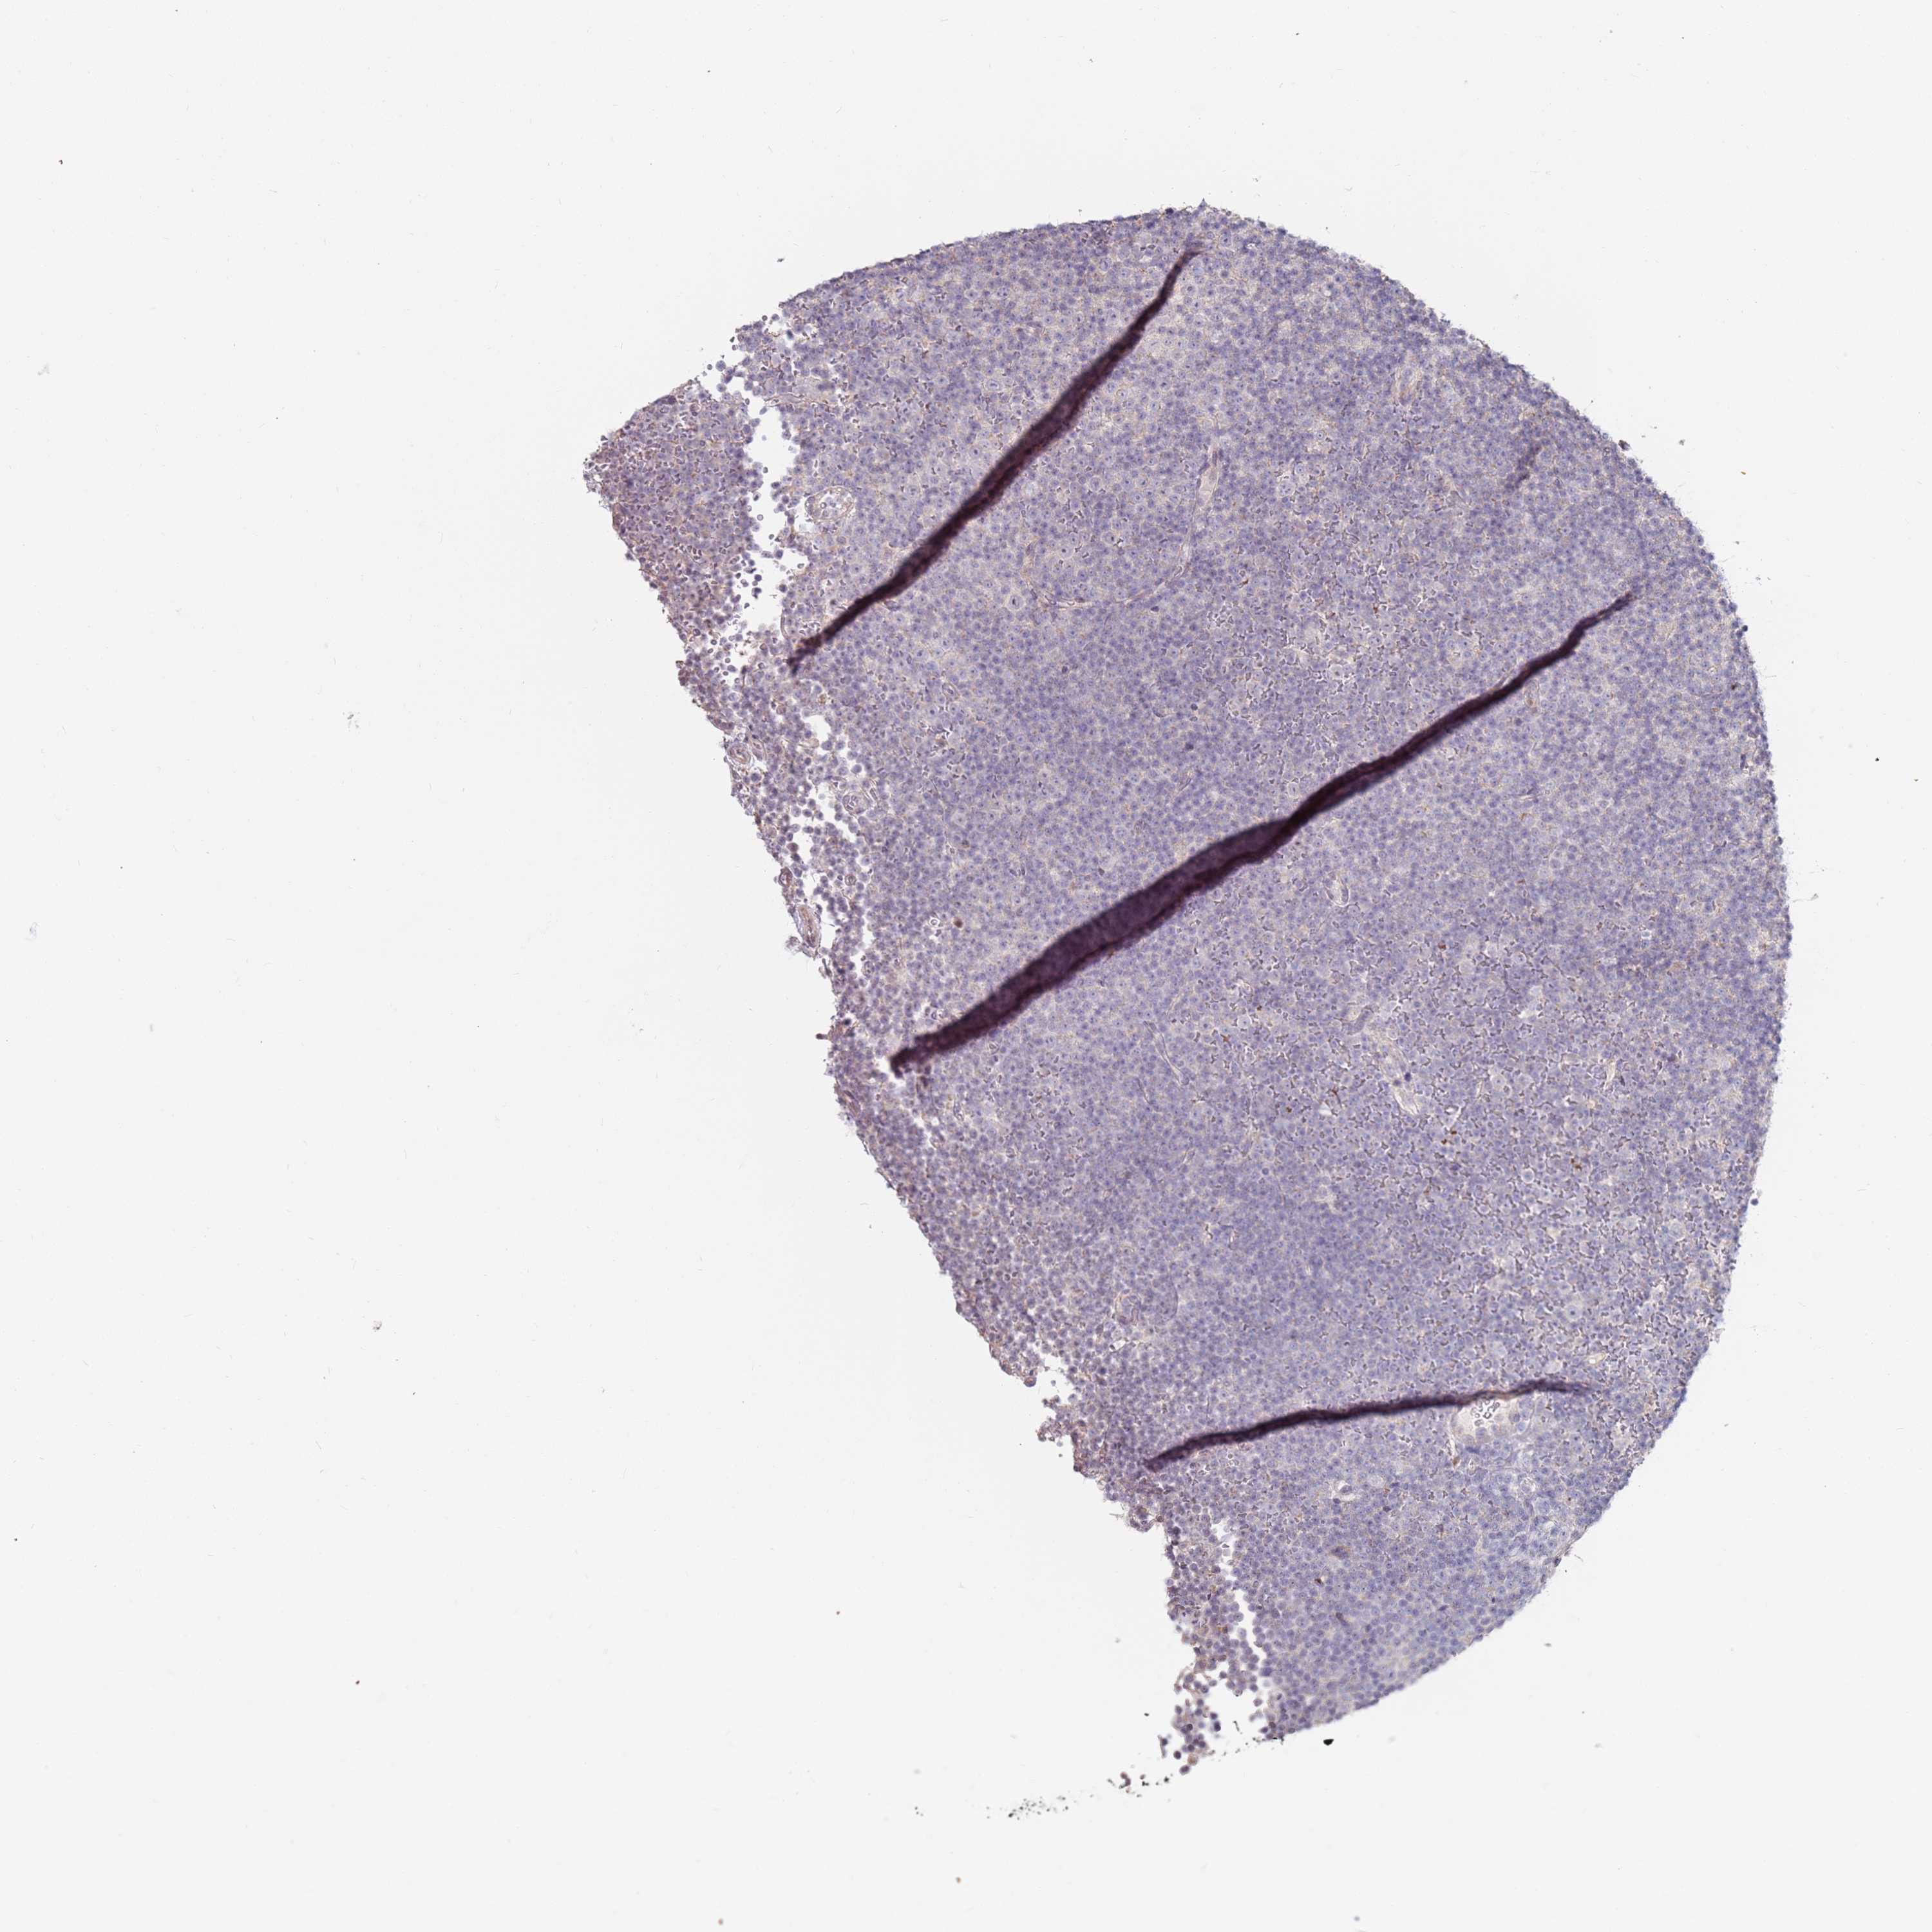

CANCER LYMPHOMA Show tissue menu

LYMPHOMA - Protein expressioni

A mouse-over function shows sample information and annotation data. Click on an image to view it in a full screen mode. Samples can be filtered based on level of antibody staining by selecting one or several of the following categories: high, medium, low and not detected. The assay and annotation is described here.

Each image is clickable and will lead to virtual microscopy that enables deeper exploration of all samples and also displays staining intensity scores, fraction scores and subcellular localization as well as patient and tissue information for each sample.

Antibody HPA039987

Antibody HPA042645

Staining

High

Medium

Low

Not detected

Intensity

Strong

Moderate

Weak

Negative

Quantity

>75%

75%-25%

<25%

None

Location

Nuclear

Cytoplasmic/membranous

Cytoplasmic/membranous,nuclear

Hodgkin's disease, NOS

Malignant lymphoma, non-Hodgkin's type, High grade

Malignant lymphoma, non-Hodgkin's type, Low grade